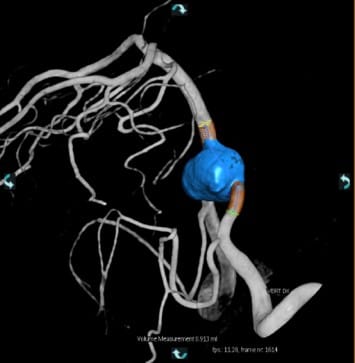

当院では、フィリップス社製3台の血管撮影装置で、各診療科がさまざまな画像下治療(Interventional Radiology:IVR)を行っています。奈良県初となる最新式装置(Philips Clarity)により、高精細な二次元画像に加え、精度の高い三次元画像を作成することで画像下治療に必要な治療手技支援画像を提供しています。

また、従来の装置では抽出困難であった冠動脈ステントや大動脈ステントの形状も明瞭に抽出できる高い画像解像度があり、頭頸部、心臓、腹部、四肢領域の画像下治療に大きな威力を発揮します。さらに最新の画像処理機能によって、従来の被ばく線量に比べ最大80%の被ばく低減を実現させています。

当院ではさまざまな分野の治療に特化した専門性の高い医療従事者からなる多職種チーム医療を推進しており、緊急検査にも積極的に即時対応しています。

脳動脈瘤やクモ膜下出血に対して金属コイルを詰め、血管を塞栓する脳動脈瘤塞栓術、脳梗塞に対して血栓を溶かして血流を再開通させる血栓溶解術、頸部動脈狭窄に対してステントを留置し血管を拡張する頸部動脈ステント留置術などを行っています。

主に肝臓癌に対して直接血管内に抗がん剤を投与した後、動脈を塞ぐ物質を注入して血管を塞栓する肝動脈化学塞栓療法(TACE)や肝動脈動注化学療法(TAI)を行っています。また、交通事故や骨盤骨折などの外傷性出血に対する緊急止血術(TAE)も積極的に行っています。

末梢動脈疾患で手足の血管が狭窄・梗塞した場合、バルーンやステントを使用して血管を広げる末梢血管治療(EVT)を行っています。